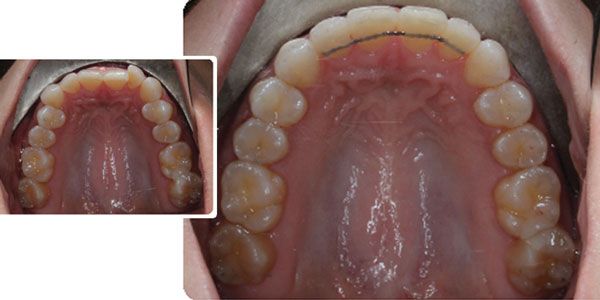

Dr. Jay B. Burton discusses the aspects of CBCT imaging that improve treatment planning and diagnostics CBCT has changed everything in my practice life — from treatment planning to treatment options to mechanotherapy, and even evaluation of treatment results. At this point, it is honestly difficult for me to imagine practicing without it. In discussions […]